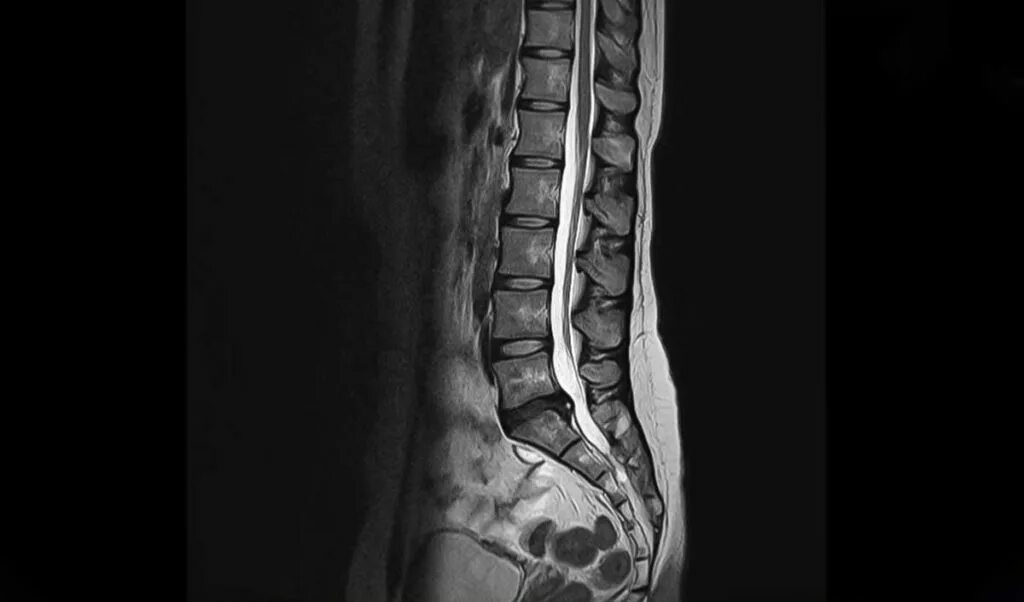

Протрузия в дуральном